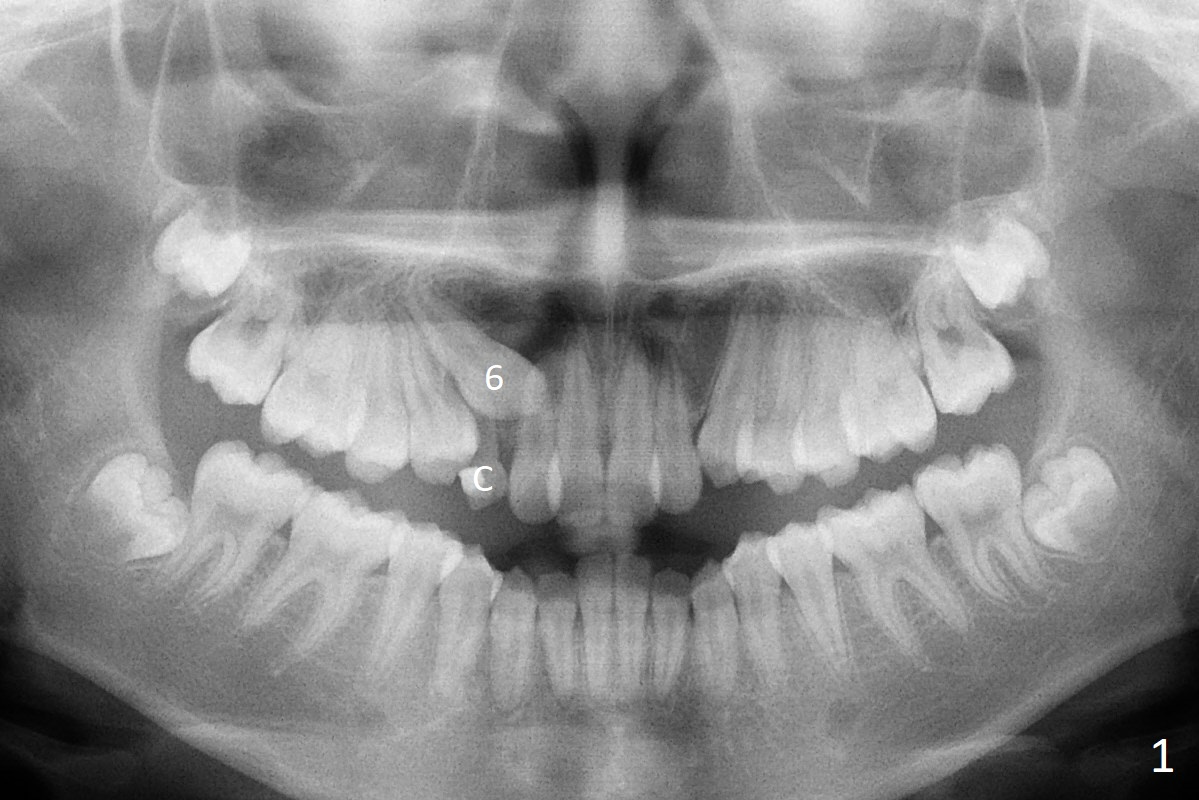

A 13-year-old woman has an impacted canine (Fig.1 (6)) and retained deciduous one (C). After initiation of orthodontics, she returns for surgical access to the impacted canine and placement of device to facilitate eruption (Fig.2,3). Incision is made buccal (Fig.4), but there is no tooth buccal (Fig.5). Extraction of the deciduous canine does not reveal the impacted one (Fig.6), but there is palatal elevation (*). Palatal access shows the impacted tooth (Fig.7) and allows placement of a retraction device (Fig.8). Careful clinical exam and CBCT are necessary diagnostic steps.